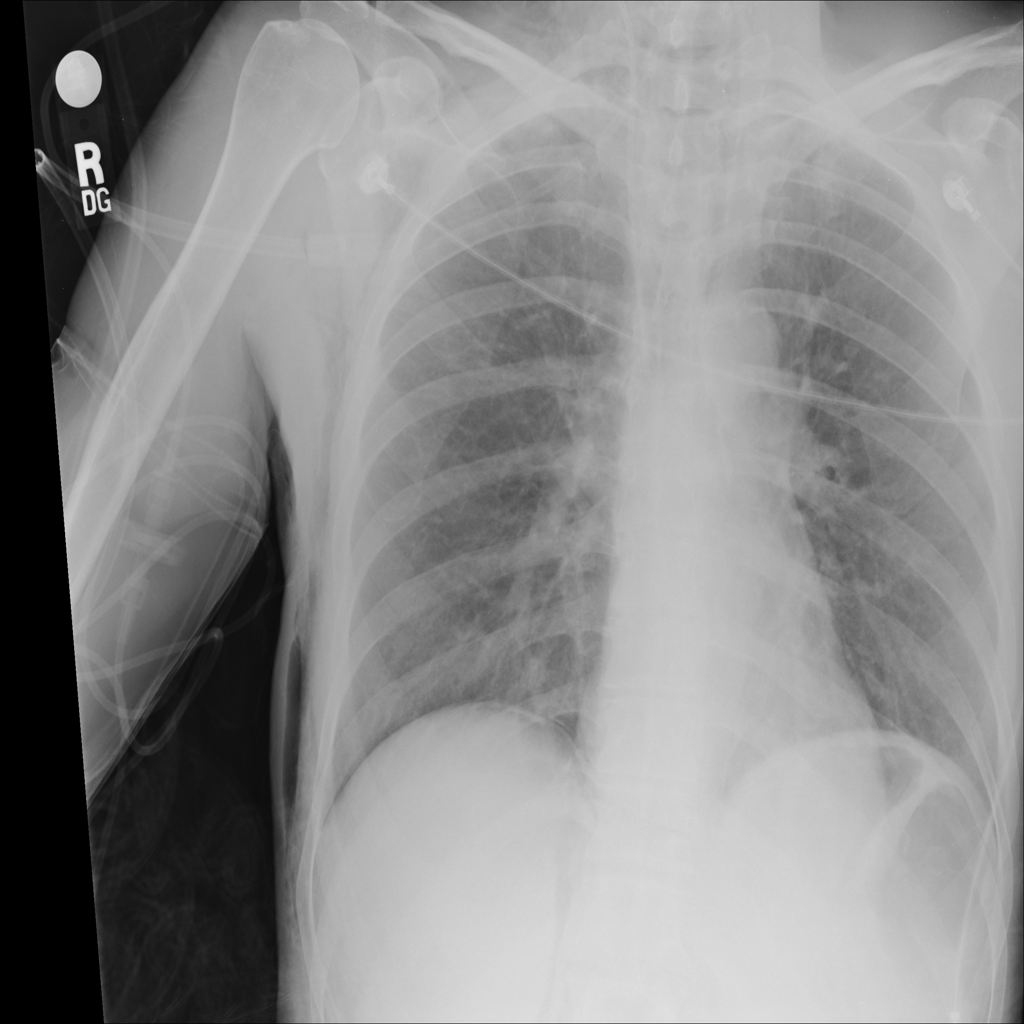

PAT-55FC · IMG-033Emphysema

PAT-55FC · IMG-033

AP